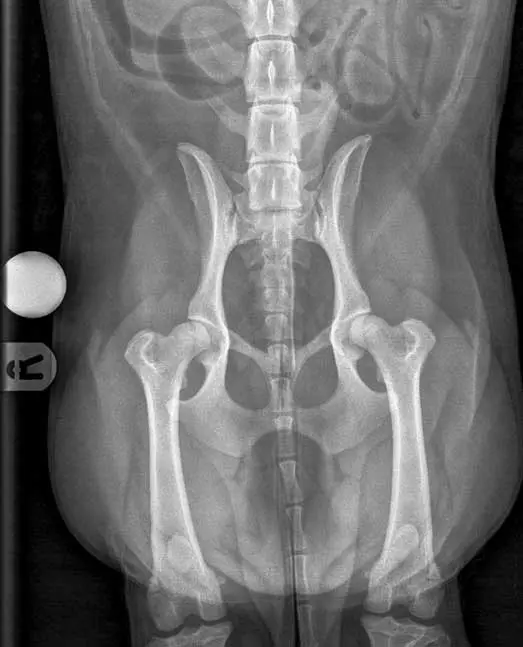

Risk assessment of all patients in for routine appointments will help to identify those that are most likely to have or develop degenerative joint disease. Risks include breeds with a genetic predisposition for OA, working and sporting dogs, dogs with a history of joint trauma or joint surgery, those that have high adiposity, or those entering senior life stage. Patients with risk factors but no symptoms may be regarded as having “pre-clinical” OA and, therefore, it is appropriate to closely monitor for development of discomfort or functional changes that could signal the onset of clinical OA, to ensure prompt intervention if needed. Diagnostics at an early stage of OA has been shown to be challenging. Radiography detects changes later than imaging such as CT, while MRI can detect even earlier changes and is the first imaging modality to be able to directly image cartilage (Figures 2 and 3; Jones et al, 2022).